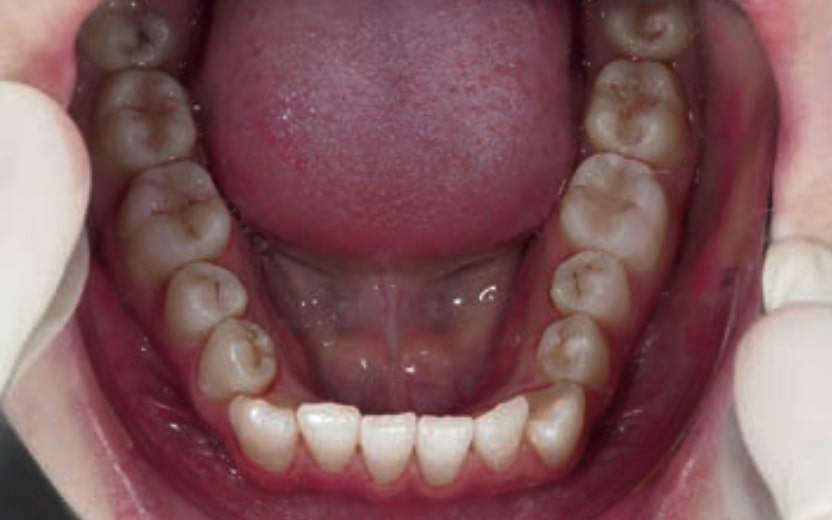

Chief complaint: The patient, a 19-year-old woman, was evaluated to undergo orthodontic treatment using the Angel Aligner Pro system. She presents with a skeletal Class III, mesofacial, with a dental Class III malocclusion and a 2 mm deviation of the lower midline to the left. Teeth 33 and 43 are out of the arch and cortical bone, with a crossbite issue on tooth 33. Fortunately, no functional issues affecting swallowing or breathing have been detected. The patient’s motivation for starting treatment was a general review of her dental and aesthetic health. The soft tissue analysis reveals mandibular protrusion that influences her facial profile. This diagnosis highlights the need for a comprehensive approach to address dental and skeletal misalignments, improving both the patient’s functionality and facial aesthetics.

- Dental Class III, 2 mm deviation of the lower midline to the left. 33 and 43 out of the arch and the cortical bone.

- Crossbite of 33.